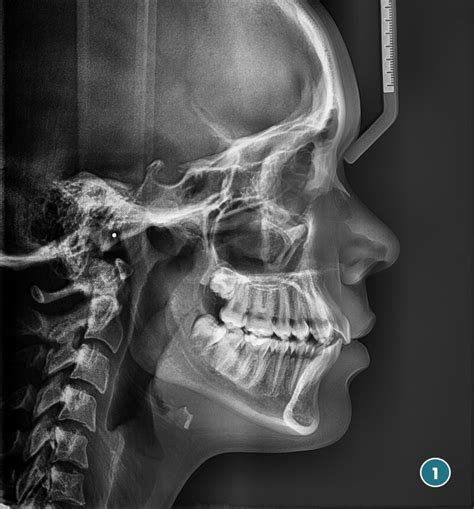

La telerradografía lateral de cráneo inicial (fig. 5) evidencia el resalte existente, con una mandíbula que presenta características típicas de tener un buen potencial de crecimiento.

Figura 5. Telerradiografía lateral de cráneo pretratamiento.

En la ortopantomografía observamos un adecuado paralelismo radicular con gérmenes de cordales en formación y con suficiente espacio habitable. También observamos imágenes radiolúcidas de caries oclusales en molares inferiores. La telerradiografía lateral de cráneo muestra una normoclusión con perfil armónico (figs. 15 y 16).

Figura 16. Telerradiografía lateral de cráneo postratamiento.